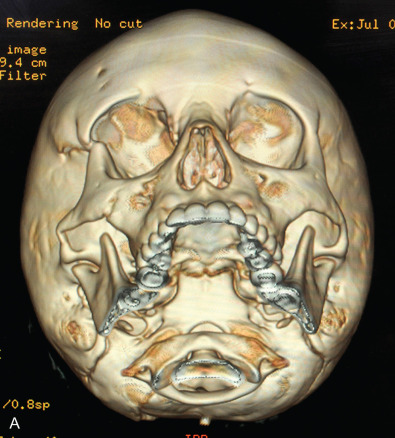

Plain films of the craniofacial skeleton, especially the midface, are of no use in the assessment of facial trauma in the pediatric population. Developing sinuses and tooth buds may obscure already overlapping planes. Computed tomography (CT) scans are necessary in order to accurately diagnose pediatric facial trauma. Fine facial cuts are necessary to adequately define facial fractures, and 3D reconstructions can be extremely useful in planning surgical intervention and teaching trainees. Cone beam CT scans and orthopantomograms (panoramic radiographs or panorex) are also useful to assess for dental injuries.

Facial fractures in children are often less displaced than those of adults and greenstick fractures are common given their more flexible bones with more mobility at suture lines and less bone mineralization. The bone exhibits a higher cancellous-to-cortical bone ratio, and without the development of the air-filled paranasal sinuses which affect the compliance of the craniofacial skeleton. At birth, the maxillary sinus is present but very small, enlarging gradually downward as the permanent dentition erupts, to fill the area previously occupied by the tooth buds. As such, it does not reach its adult size until eruption of the third molars. Ethmoid air cells are also usually present at birth, slowly expand, and are the first sinuses fully developed, which occurs around puberty ( Fig. 2.4.2 ). The sphenoid sinus first appears around age 2 and continues to enlarge until skeletal maturity, with some further septation into adulthood. The frontal sinus first appears at age 5 and continues to expand into late teen years. Increased soft tissue padding, thicker fat pads, and the strong, developing tooth buds within the maxilla and mandible also provide increased resistance to complete fractures ( Fig. 2.4.3 ). While these factors act to provide protection for the pediatric skeleton, a higher impact force per unit area is required for the facial bones to fracture in children compared with their adult counterparts and as such, there may be a higher incidence of associated injuries. The unique nature of the elastic compliant pediatric craniofacial skeleton can result in greenstick fractures and discontinuity between fracture zones ( Fig. 2.4.4 ).